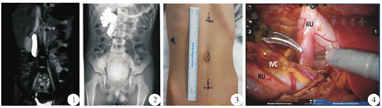

患儿 男,7岁。因"腹痛检查发现右肾积水1个月"入院。孕期产检未发现胎儿肾积水,患儿既往曾因法洛四联症行手术治疗。专科查体无明显异常。当地医院B型超声检查示右肾积水,考虑右侧输尿管上段狭窄可能;肾动态肾图检查示右肾肾小球滤过率(glomerular filtration rate,GFR)为44.28 ml/min,左肾GRF为46.25 ml/min,右肾GFR未见明显异常,但未见明显排泄。入我院后行磁共振泌尿系统水成像(magnetic resonance urography,MRU)检查,提示右肾中度积水,右侧输尿管上段扩张,中段狭窄且行走迂曲(图1)。行膀胱镜下逆行造影检查示右肾及右输尿管上段扩张积液,右输尿管中上段(约平L2-3椎体水平)走行迂曲(图2)。考虑诊断腔静脉后输尿管,行机器人辅助腹腔镜下右侧输尿管成形术。全身麻醉后导尿,取45°健侧卧位,垫高腰部。于脐左缘处取12 mm切口,置入腹腔镜套管。于前正中线脐上6 cm及脐下6 cm各取一8 mm切口(图3),镜头直视下置入操作套管,安装操作臂。术中沿结肠旁沟打开侧腹膜,于右肾下极暴露输尿管,见输尿管上段及肾盂扩张明显,输尿管中段走行于下腔静脉后侧(图4)。于腔静脉水平离断输尿管,使离断后的输尿管复位于下腔静脉前方,将切口下角向远端输尿管外侧壁纵行延长,至切开正常输尿管壁1~1.5 cm处(距离断点3.5 cm处可见输尿管相对狭窄),修剪近端输尿管切口边缘呈楔形。间断吻合输尿管。术中留置6F双J管1根。患儿手术顺利,手术时间3 h,输尿管游离、离断、吻合时间为80 min。术中出血约30 ml。术后病理检查结果示黏膜被覆尿路上皮灶性脱落,黏膜下水肿伴充血出血,各层少许炎症细胞散在浸润,血管充血。患儿恢复良好,无不适主诉,术后5 d拔除导尿管后出院。术后6周拔出双J管,复查彩色多普勒超声提示右肾积水较前明显缓解。术后半年随访患儿腹痛症状较前改善,偶有轻微发作。本次研究患儿家属均知情同意。

注:RU,腔静脉后输尿管;IVC,下腔静脉